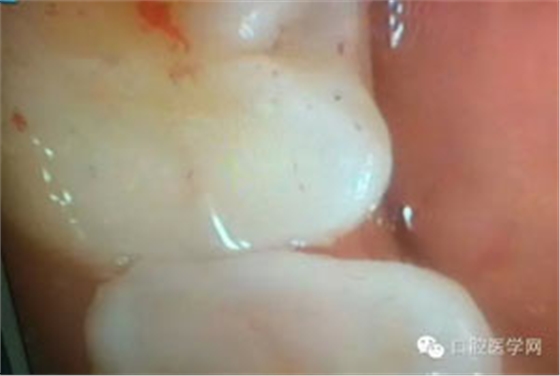

病例1:患者迫切希望保留自己的這一顆牙齒,根尖周陰影比較大,二度松動(dòng).而且旁邊有種植修復(fù)體,和患者溝通好后,治療好后觀察一個(gè)月后冠修復(fù),因?yàn)橛蟹N植的后期修復(fù),所以有了機(jī)會(huì)觀察,術(shù)后三個(gè)月和術(shù)后四個(gè)月,根尖恢復(fù)的還算不錯(cuò),希望能夠繼續(xù)觀察下去.這樣子的病例,做的時(shí)候我們一定要非常的小心,和患者要有充分的溝通以及不同科室的溝通然后決定怎么樣做比較好,假如就是出現(xiàn)了問(wèn)題,到時(shí)候我們也比較好處理些,免得我們自己到時(shí)候不好收?qǐng)觥?/span> 病例2:364647中齲的樹(shù)脂充填,現(xiàn)在樹(shù)脂的充填材料非常之多,有些時(shí)候,我們感覺(jué)有了好的材料我們就可以做出好的修復(fù),可是這是在我們有扎實(shí)的基本功的基礎(chǔ)上的,我們可以沒(méi)有那么好的樹(shù)脂,那么多的顏色選擇,修復(fù)的那么的逼真,但是我們至少要恢復(fù)患者牙齒的功能,將腐質(zhì)去除干凈,薄壁弱尖消除掉,選擇好適應(yīng)癥,給患者以盡可能好的修復(fù)。 來(lái)源于KQ88